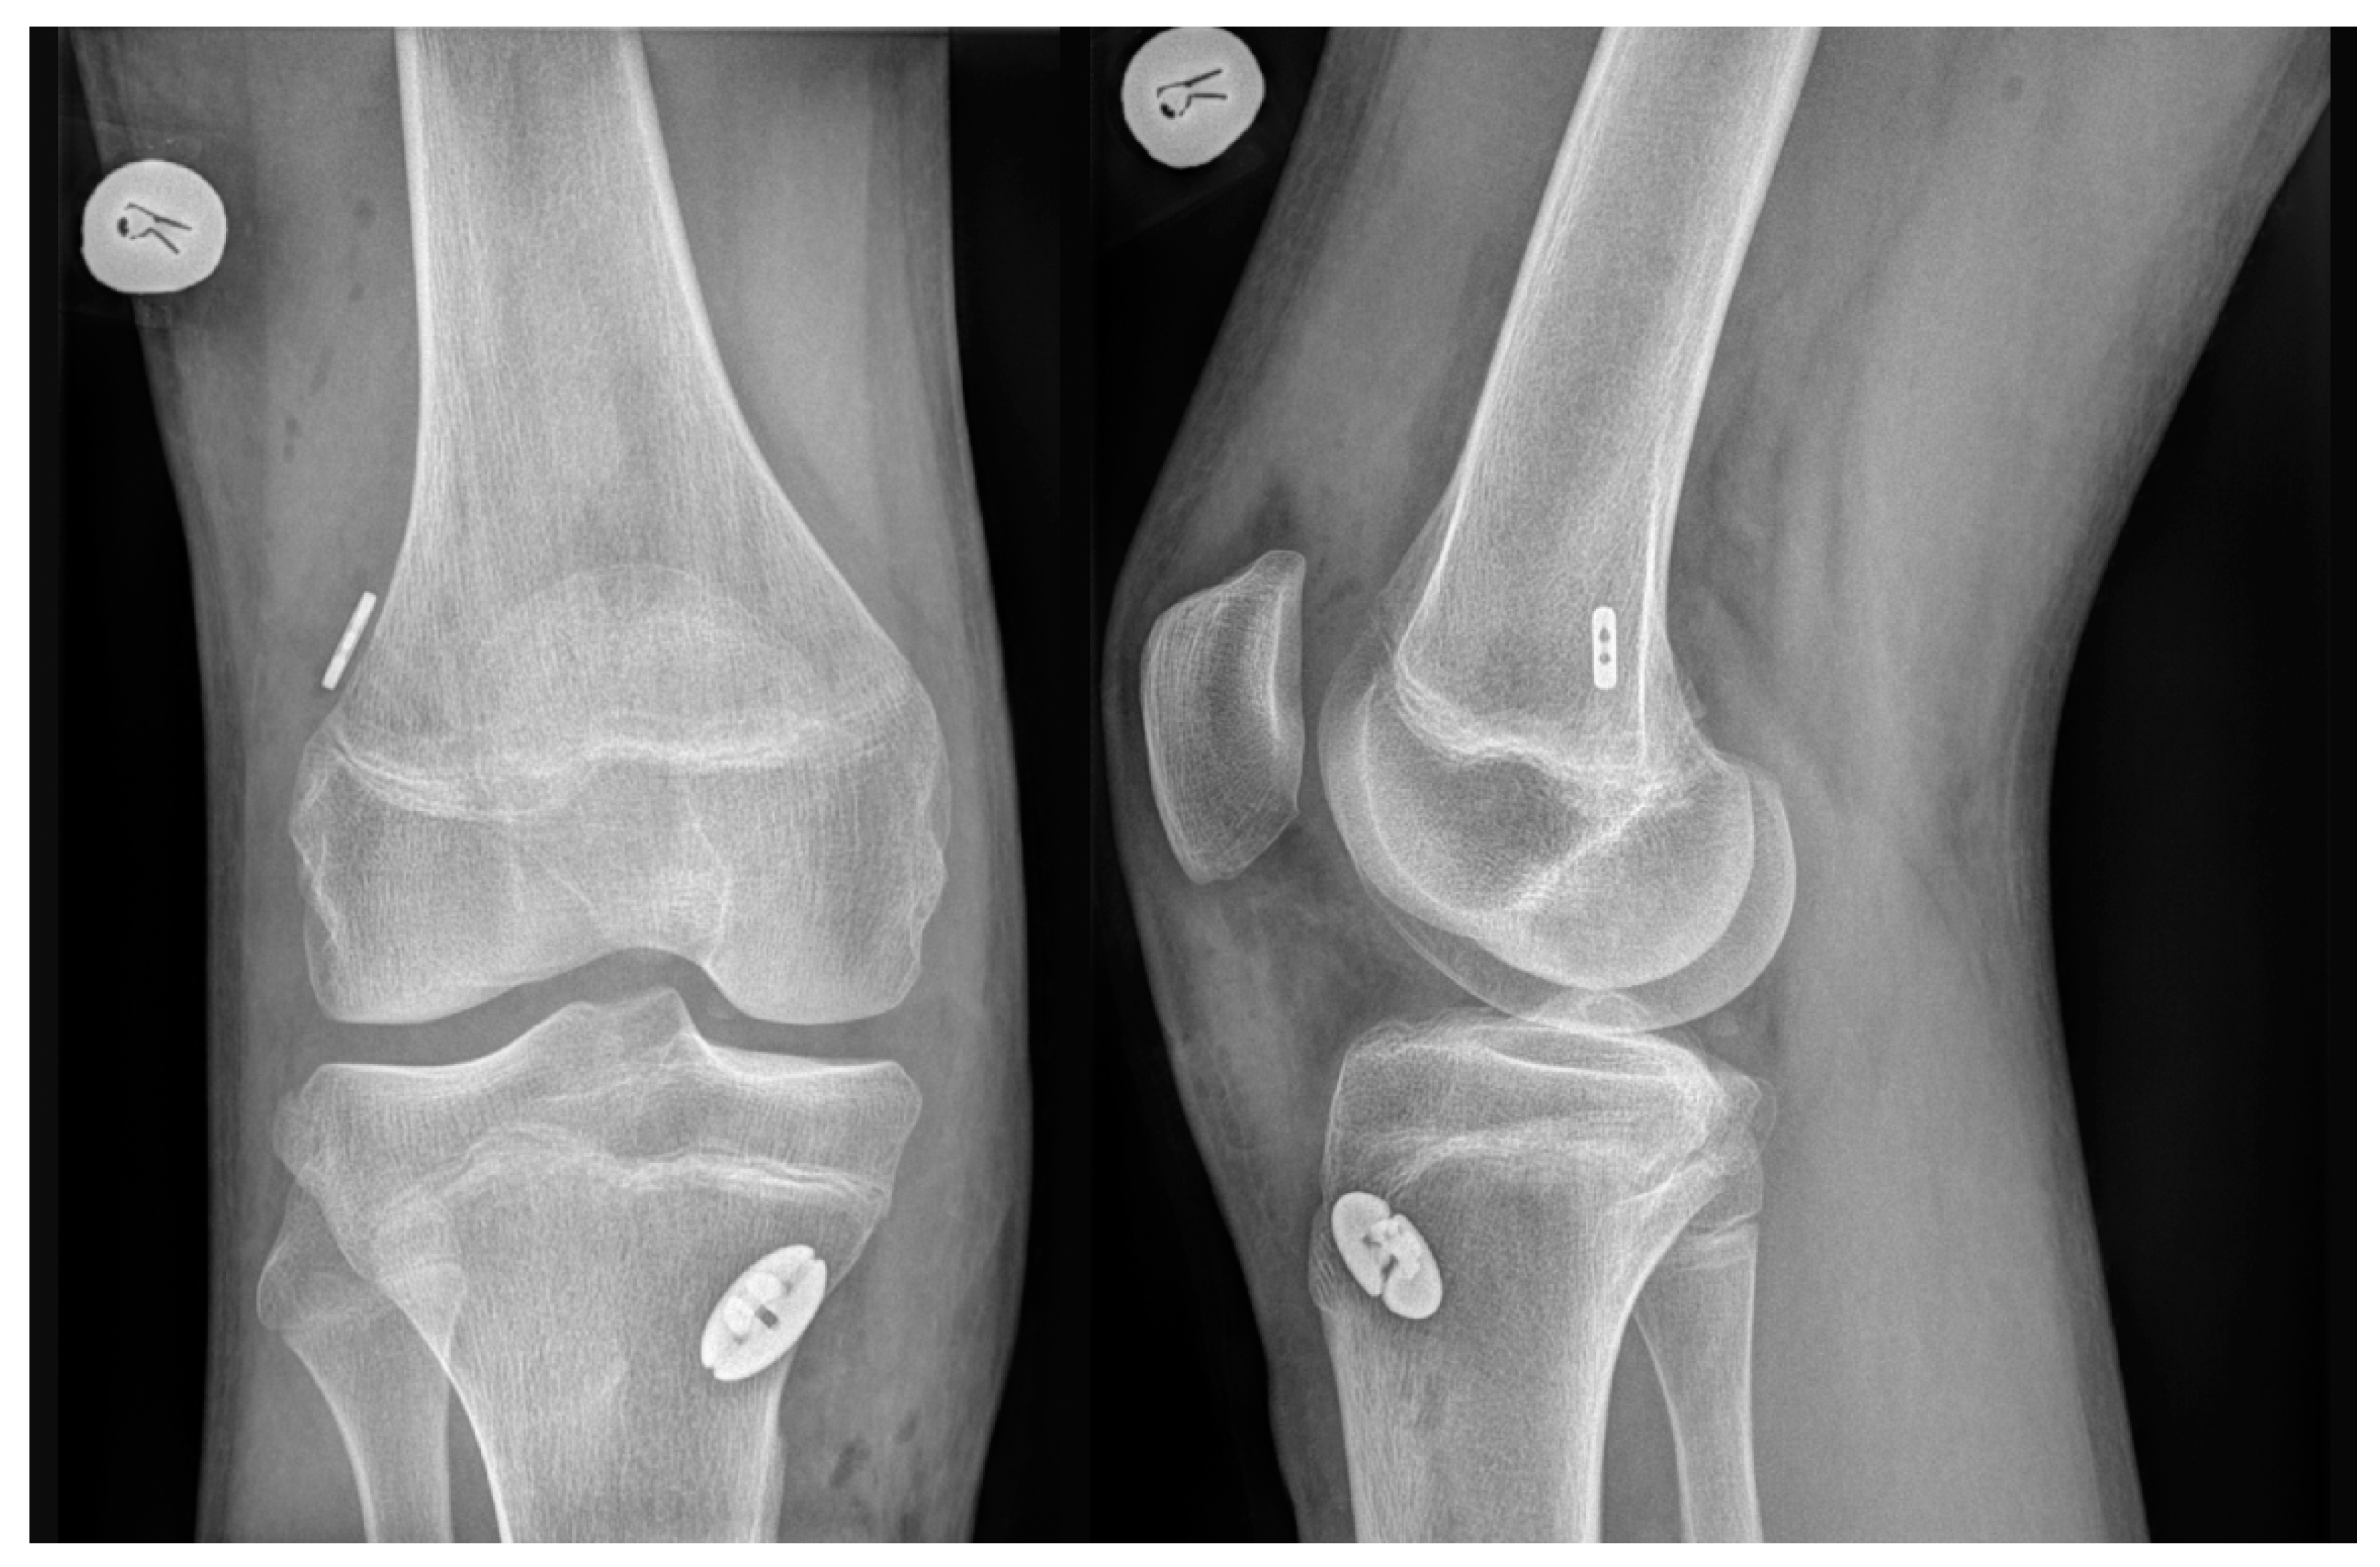

2.2. Surgical Technique

2.2.1. Hamstring Tendon Autograft

2.2.2. Quadriceps Tendon Autograft